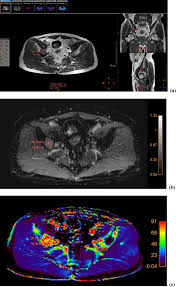

Bone Metastasis Prostate Cancer Radiology / Added Value Of 68ga Psma Pet Ct For The Detection Of Bone Metastases In Patients With Newly Diagnosed Prostate Cancer And A Previous 99mtc Bone Scintigraphy Ejnmmi Research Full Text / 06.03.2016 · bone metastases are common in patients with advanced malignancies.. Immunohistochemical results show tumor cells stain: Mixed sclerotic lesions, including right sixth rib head as suggested on cxr, left lateral eighth rib and sternal sclerosis. Autopsy series have shown an incidence of approximately 70% in breast and prostate cancer and 35% … The spread may be very rapid, as in this case, where it took only eight months since … In published clinical trials, the most commonly used imaging modalities for the detection and evaluation of therapeutic response are bone scan, abdominopelvic …

Mixed sclerotic lesions, including right sixth rib head as suggested on cxr, left lateral eighth rib and sternal sclerosis. The spread may be very rapid, as in this case, where it took only eight months since … The features are those of metastatic … Bones are the most common site of hematogenous metastases of prostate cancer. 06.03.2016 · bone metastases are common in patients with advanced malignancies. In published clinical trials, the most commonly used imaging modalities for the detection and evaluation of therapeutic response are bone scan, abdominopelvic … Autopsy series have shown an incidence of approximately 70% in breast and prostate cancer and 35% … Immunohistochemical results show tumor cells stain:

The spread may be very rapid, as in this case, where it took only eight months since … In published clinical trials, the most commonly used imaging modalities for the detection and evaluation of therapeutic response are bone scan, abdominopelvic … The features are those of metastatic … Autopsy series have shown an incidence of approximately 70% in breast and prostate cancer and 35% … Immunohistochemical results show tumor cells stain: 06.03.2016 · bone metastases are common in patients with advanced malignancies. Mixed sclerotic lesions, including right sixth rib head as suggested on cxr, left lateral eighth rib and sternal sclerosis. Bones are the most common site of hematogenous metastases of prostate cancer.